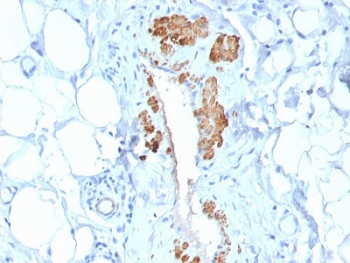

IHC: Formalin-fixed, paraffin-embedded human angiosarcoma stained with SMMHC antibody (MYH11/923).